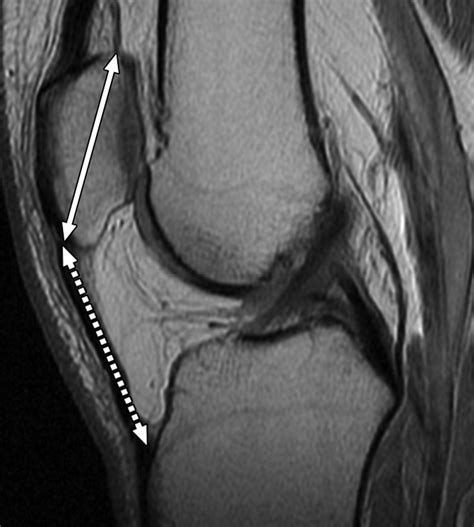

Hoffa’s Fat Pad, also known as the infrapatellar fat pad, is a specialized adipose tissue located in the anterior compartment of the knee. It is situated between the patellar tendon and the tibia, providing a protective layer that helps distribute forces and reduce wear and tear on the knee joint. The pad is richly innervated with sensory nerves, making it sensitive to pressure and movement.

Diagnosing conditions related to Hoffa’s Fat Pad typically involves a combination of physical examination, medical history, and imaging tests. Treatment options vary depending on the severity and underlying cause of the condition.

• Imaging tests: X-rays, MRI, or ultrasound may be used to visualize the fat pad and surrounding structures.